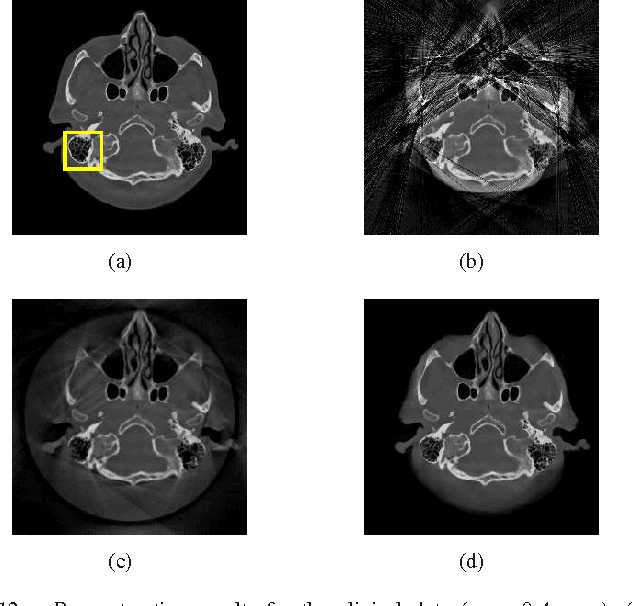

Abstract:When a measurement falls outside the quantization or measurable range, it becomes saturated and cannot be used in classical reconstruction methods. For example, in C-arm angiography systems, which provide projection radiography, fluoroscopy, digital subtraction angiography, and are widely used for medical diagnoses and interventions, the limited dynamic range of C-arm flat detectors leads to overexposure in some projections during an acquisition, such as imaging relatively thin body parts (e.g., the knee). Aiming at overexposure correction for computed tomography (CT) reconstruction, we in this paper propose a mixed one-bit compressive sensing (M1bit-CS) to acquire information from both regular and saturated measurements. This method is inspired by the recent progress on one-bit compressive sensing, which deals with only sign observations. Its successful applications imply that information carried by saturated measurements is useful to improve recovery quality. For the proposed M1bit-CS model, alternating direction methods of multipliers is developed and an iterative saturation detection scheme is established. Then we evaluate M1bit-CS on one-dimensional signal recovery tasks. In some experiments, the performance of the proposed algorithms on mixed measurements is almost the same as recovery on unsaturated ones with the same amount of measurements. Finally, we apply the proposed method to overexposure correction for CT reconstruction on a phantom and a simulated clinical image. The results are promising, as the typical streaking artifacts and capping artifacts introduced by saturated projection data are effectively reduced, yielding significant error reduction compared with existing algorithms based on extrapolation.